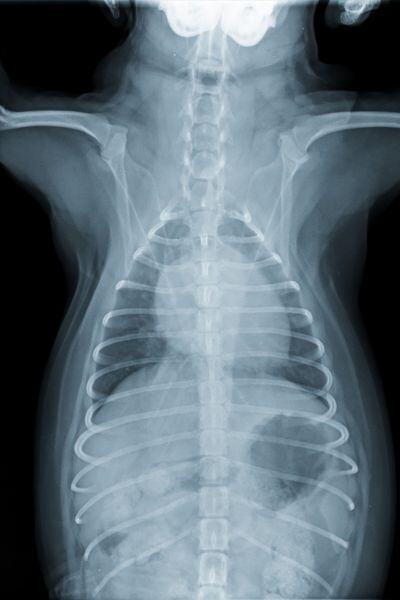

Dogs predisposed to heart conditions should have, at minimum, yearly diagnostic testing, like X-rays or echocardiograms.

Imaging tests usually include chest X-rays with vertebral heart scoring, which is based on several measurements of the heart silhouette and will vary with the size and breed of your dog.